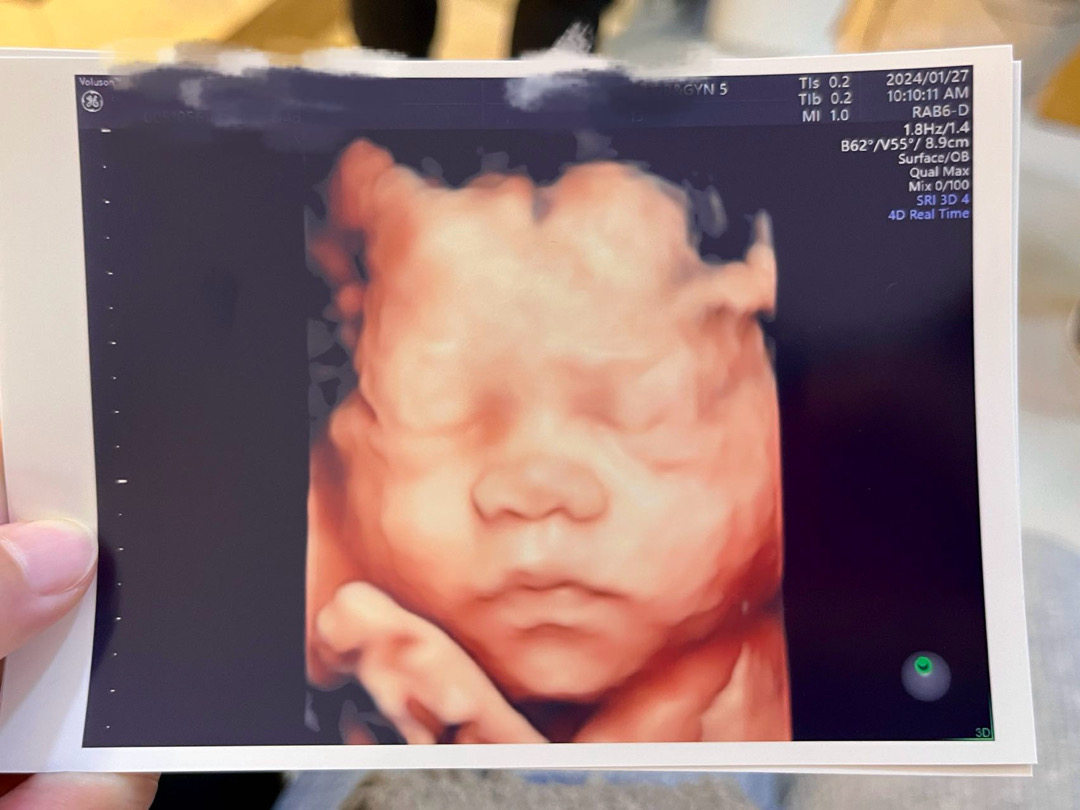

28주 입체초음파 찍고 왔어요🥰

어제 입체초음파 찍고 왔는데 사진 너무 선명하게 잘 나왔어요!!다들 남편이랑 뚝닮았다고 하네요🤣